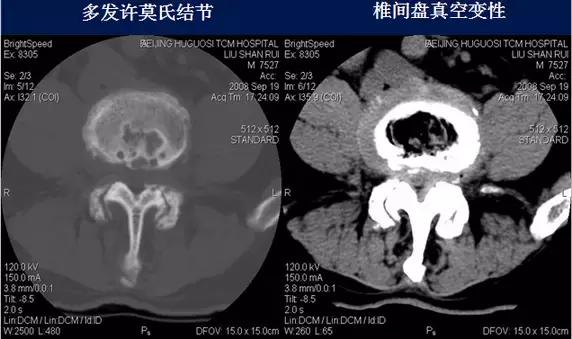

2、椎间盘真空变性:椎间盘见气体密度影,形成真空征。

3、许莫氏结节(schmorl’s nods):又称髓核压迹。